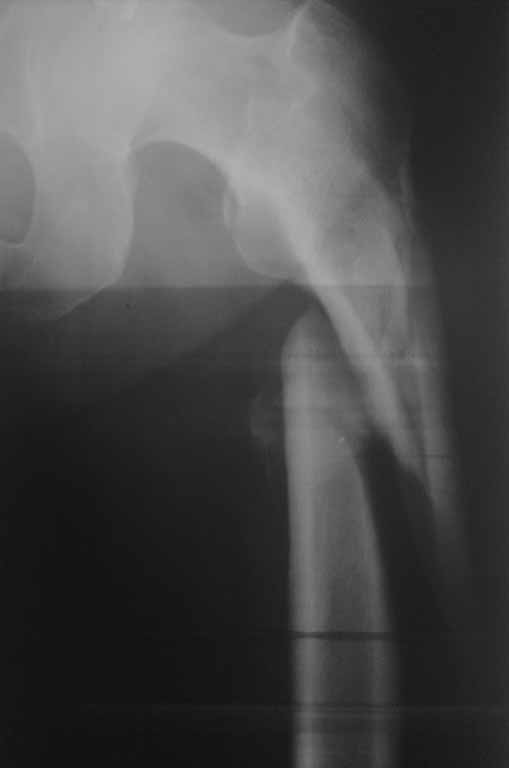

Перелом бедра и голени

Поступил пациент почти через 3 месяца после травмы. Упал с лестницы. Лечился в ЦРБ. Слева чрезвертельноподвертельный перелом с формированием уже костной мозоли в не очень правильном положении. Справа голень в задней гипсовой лонгете.

Состояние мягких тканей хорошее. Из имеющихся фиксаторов: длинный PFN - 340mm (мне кажется коротковат). Голенные стержни деост все типоразмеры. Пластины LCP DF, LCP, на голень лист клевера болкируемые любой длины, 1/3 трубки. Есть ЭОП, ортопедический1 стол. Прошу высказать мнения об очередности операций и предпочтительной техники фиксации. Заранее спасибо.